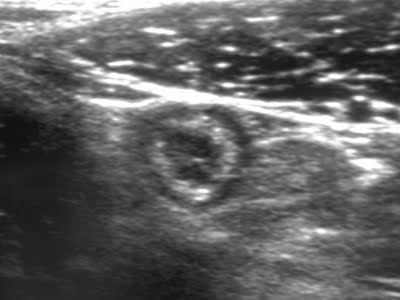

Abdominal ultrasonography is the first-line imaging modality in patients with acute abdominal pain suspected of appendicitis because it is inexpensive, rapid, easy to perform, and free of ionizing radiation; therefore, it is especially useful in children and pregnant women. The technique used is graded-compression ultrasonography to displace adjacent bowel loops.

Ultrasonographic findings of appendicitis include a blind-ended tubular structure arising from the cecum, with a diameter >6 mm, wall thickness >3 mm, absent peristalsis, non-compressibility, a target sign on transverse view, and a finger-like appearance on longitudinal view.

Figure 3. Ultrasonographic appearance of appendicitis